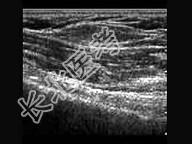

- 单项选择题患者,男, 28岁,皮下扪及肿块六月余。超声检查压之不变形。声像图提示 ( )

A、皮脂腺囊肿

B、脂肪瘤

C、纤维瘤

D、皮下组织增厚

E、炎症